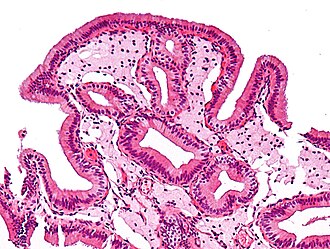

Gallbladder cholesterolosis. H&E stain.

LM abundant foamy macrophages in the lamina propria, +/-papillary hyperplasia

Features:

• Numerous foamy macrophages in the lamina propria.

• +/-Papillary hyperplasia.[1]